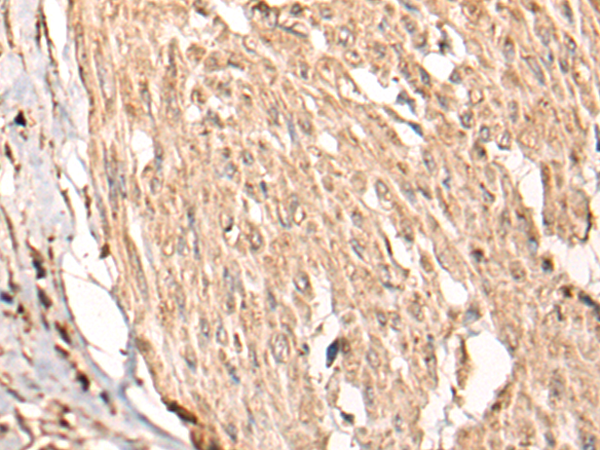

ELISA, IHC |

IHC positive control: |

Human cervical cancer |

IHC Recommend dilution: |

40-200 |